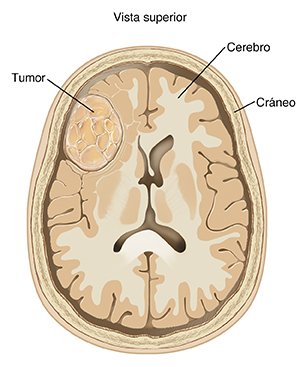

Un tumor cerebral es una masa de células anormales que se forma en el cerebro. Hay muchos tipos de tumores cerebrales. Quizás empezó en el cerebro (tumores primarios) o se propagó al cerebro desde otra parte del cuerpo (tumores metastásicos). Los tumores cerebrales pueden ser de crecimiento lento, de propagación poco probable y no cancerosos (benignos). O pueden ser de crecimiento rápido, propagarse a otras partes del cerebro y ser cancerosos (malignos). Los dos tipos de tumores cerebrales pueden causar problemas graves si presionan y dañan el tejido cerebral normal. Los síntomas dependerán del tipo de tumor, del tamaño y de la ubicación en el cerebro.